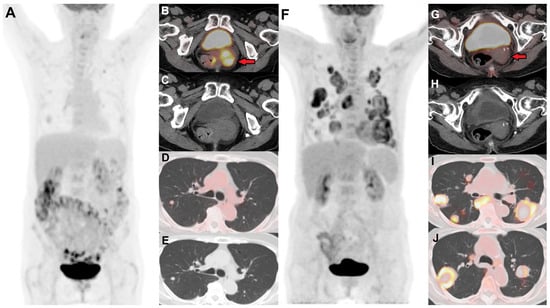

2.3. FDG PET in Response Assessment

- Sanei Sistani, S.; Parooie, F.; Salarzaei, M. Diagnostic Accuracy of 18F-FDG-PET/CT and MRI in Predicting the Tumor Response in Locally Advanced Cervical Carcinoma Treated by Chemoradiotherapy: A Meta-Analysis. Contrast Media Mol. Imaging 2021, 2021, 8874990. [Google Scholar] [CrossRef]

- Dendl, K.; Koerber, S.A.; Finck, R.; Mokoala, K.M.G.; Staudinger, F.; Schillings, L.; Heger, U.; Röhrich, M.; Kratochwil, C.; Sathekge, M.; et al. 68Ga-FAPI-PET/CT in Patients with Various Gynecological Malignancies. Eur. J. Nucl. Med. Mol. Imaging 2021, 48, 4089–4100. [Google Scholar] [CrossRef]

- Mokoala, K.; Maserumule, L.; Mokgoro, N.; Ndlovu, H.; Ismaila, A.; Ebenhan, T.; Zeevaart, J.R.; Sathekge, M. Intraindividual Comparison of 68Ga-FAPI PET/CT with 18F-FDG PET/CT for Imaging of Cancer of the Cervix. J. Nucl. Med. 2024, 65, 242174. [Google Scholar]

- Wegen, S.; Roth, K.S.; Weindler, J.; Claus, K.; Linde, P.; Trommer, M.; Akuamoa-Boateng, D.; van Heek, L.; Baues, C.; Schömig-Markiefka, B.; et al. First Clinical Experience With [68Ga]Ga-FAPI-46-PET/CT Versus [18F]F-FDG PET/CT for Nodal Staging in Cervical Cancer. Clin. Nucl. Med. 2022, 48, 150. [Google Scholar] [CrossRef] [PubMed]